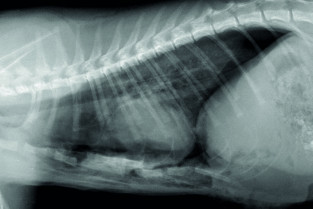

• adopter une méthodologie pour interpréter les affections de la cage thoracique, de la plèvre, du médiastin et des poumons chez les carnivores domestiques ;

• décrire l’aspect normal et anormal de la cage thoracique, de la plèvre, du médiastin et des poumons chez les carnivores domestiques.

Technique et anatomie radiographique de la cage thoracique, de la plèvre et du médiastin

Sémiologie et interprétation des anomalies de la cage thoracique, de la plèvre et du médiastin

TP de lecture de radiographies numériques sur station de travail